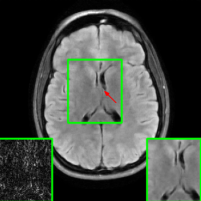

Here, we employ the fastMRI+ dataset to assess our approach’s image reconstruction capability. For the training phase, we employ the original fastMRI brain dataset, which excludes lesion cases, as the basis for training all methods. During the testing phase, however, we utilize the lesion dataset. Table II shows the results, where our method reports the highest PSNR and SSIM values compared to other baselines. It is important to highlight that, unlike the cases of additive k-space noise and training/testing sampling protocol and undersampling rate disparities, the improvements observed from utilizing our method with unseen lesions are somewhat marginal as seen from the average PSNR and SSIM results (at least 1.2 dB PSNR improvement when compared to the 2nd best results). Additionally, visualizations are provided Figure 13 where we highlight the nonspecific white matter lesion area. As observed, both visually and in terms of PSNR values, our approach reports improved results when compared to the other baselines.

Figure 10 presents visual comparison of image reconstructions and their associated reconstruction errors within a closely examined region. Each image in the figure includes two inset panels in the bottom-left and bottom-right corners. The bottom-left inset panel, enclosed within a green bounding box, serves as a reference for the region of interest in the image. In contrast, the bottom-right inset panel depicts an error map in relation to the ground truth. Notably, our method stands out in its ability to capture more features from the original image, surpassing the performance of alternative methods (as also evident from the reported PSNR values).

V-D2 Robustness to Different Sampling Protocols & Undersampling Rates